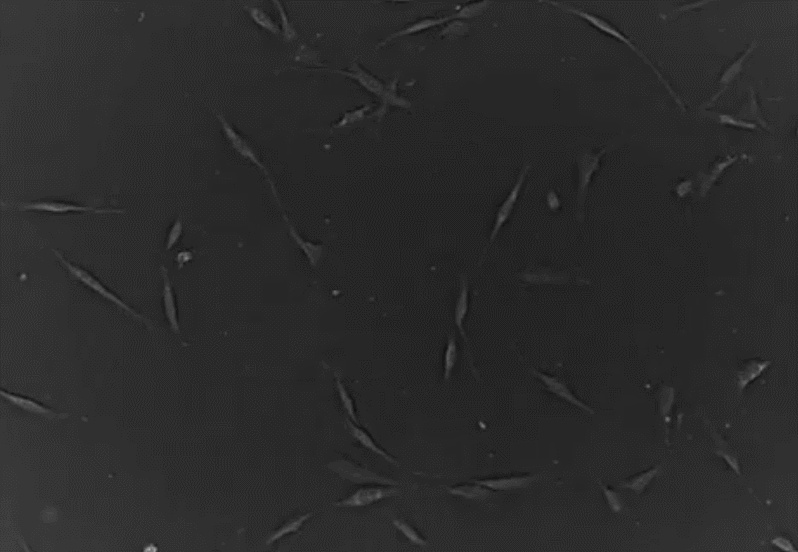

¡÷  ÔÚÅàÑøÆ¿ÖзÖÉ¢µÄ¼ä³äÖʸÉϸ°û